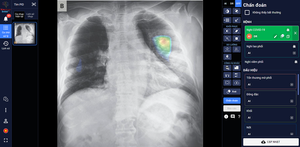

DrAid – phần mềm chẩn đoán hình ảnh y tế đang gây ấn tượng mạnh với thế giới trong vai trò trợ lý đắc lực giúp chẩn đoán và điều trị các bệnh lý về Tim Phổi – Xương.

Sản phẩm DrAid™ của VinBrain vừa chính thức được Cơ quan Quản lý Thực phẩm và Dược phẩm Hoa Kỳ (FDA) ra công văn chấp thuận.

VinBrain cùng Bệnh viện Đại học Y dược TP.HCM phát triển ứng dụng công nghệ AI phát hiện, chẩn đoán ung thư gan.